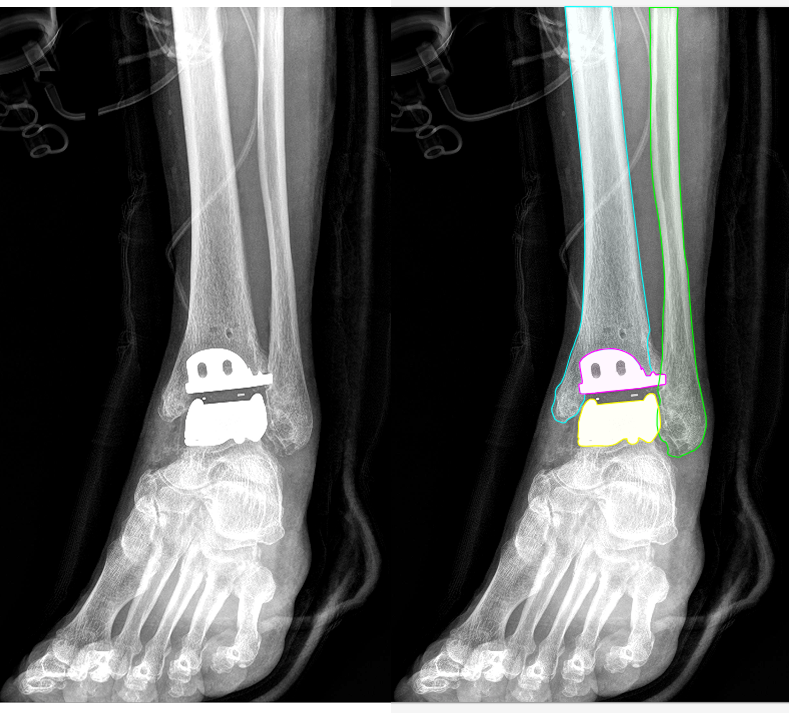

AI 모델이 의료 영상을 효과적으로 학습할 수 있도록, 각 부위와 촬영 방식(AP, Lateral 등)에 맞추어 세그멘테이션(Segmentation), 키포인트(Keypoint), 바운딩 박스(Bounding box) 등 세 가지 방식의 정밀 라벨링 작업을 복합적으로 수행했습니다.

발목(Ankle): 경골, 비골, 거골에 대한 세그멘테이션 및 경골 바깥쪽 끝에 대한 키포인트를 지정했습니다.